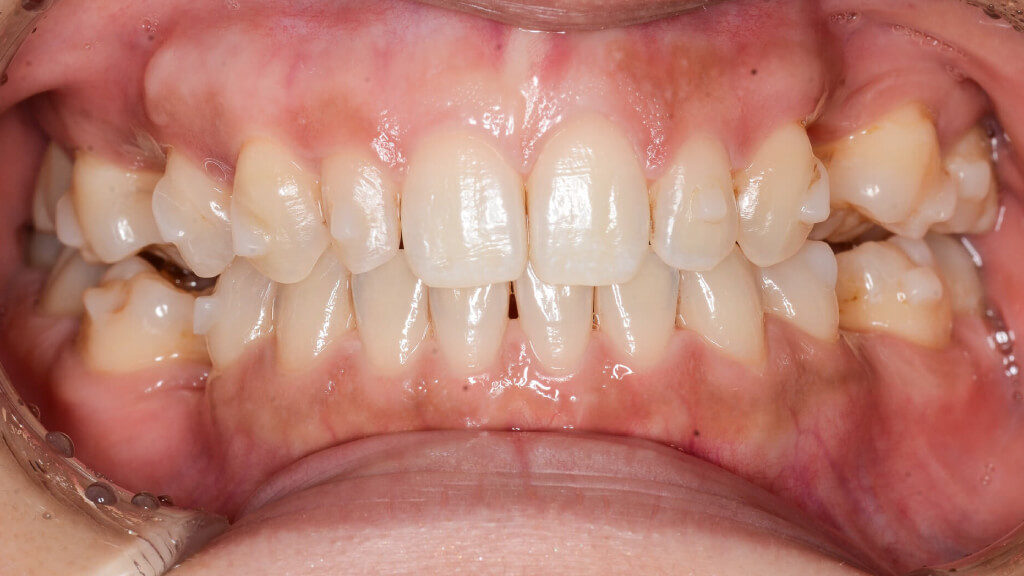

矯正治療開始から約1年後

6.術前正面1年経過

左上1番・2番の歯は、治療前には下の歯より内側に入ってしまうクロスバイト(反対咬合)の状態でしたが、インビザラインによる矯正治療によって歯の位置関係が改善し、かみ合わせも整ってきました。

7.術前左1年経過比較

また、矯正治療によってインプラントを埋入するためのスペースもしっかり確保できたため、このタイミングでインプラントの埋入手術を行います。